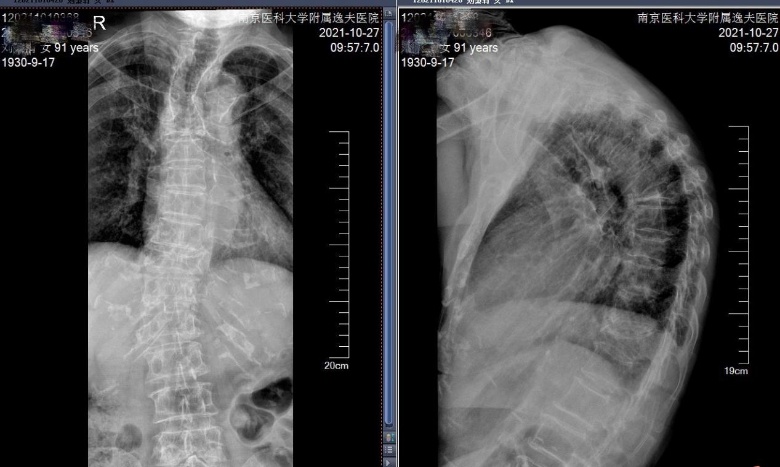

91岁老太两次胸椎骨折致驼背,骨科微创技术让她又挺直"腰杆"